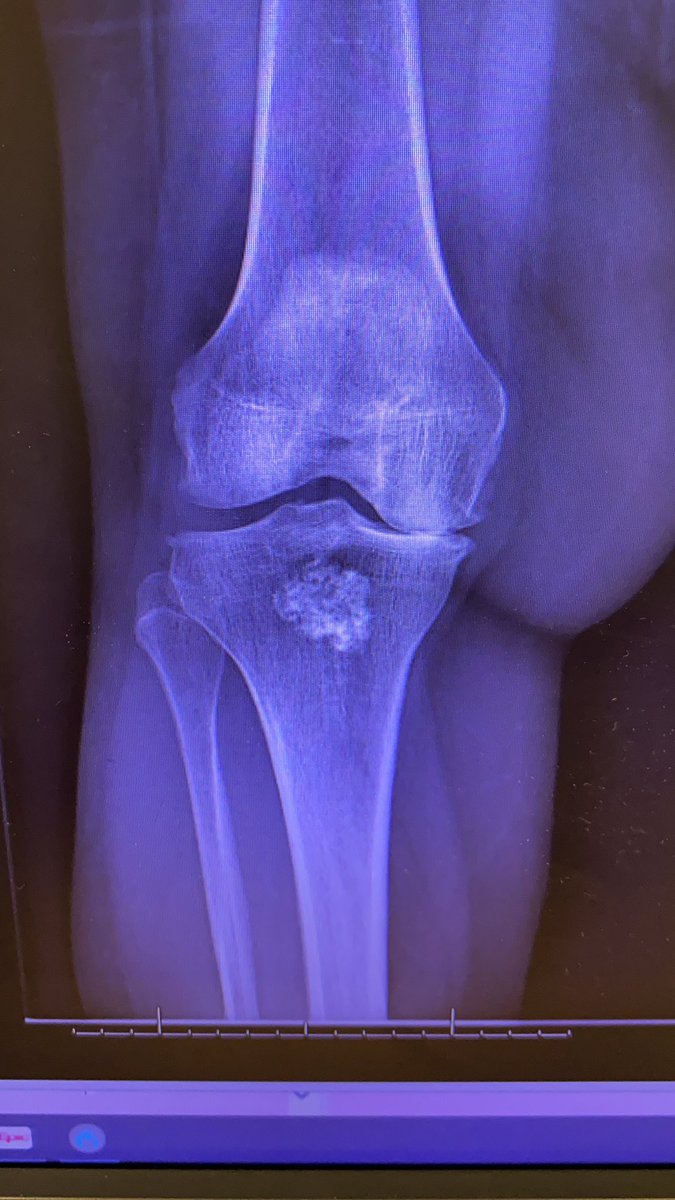

wanting TKA. Allergy to nickel and cement on now two different patch tests. Yes not perfect test but I live in colorado so a real thing here. Benign enchondroma in tibia. How are you dealing with this?? @BoneDocMMD @DrLeeRubin @jointdocShields @generalorthomd @RafaSierra5

Tough case @jointdocShields @EdinburghKnee @DrLeeRubin @BoneDocMMD and whomever else couldn’t add everyone #61y/o physician. Wants TKA. Deformity and remote infection. Infection workup negative. Stage? All at once? Or patient is enquiring about DFR. Thx for your thoughts